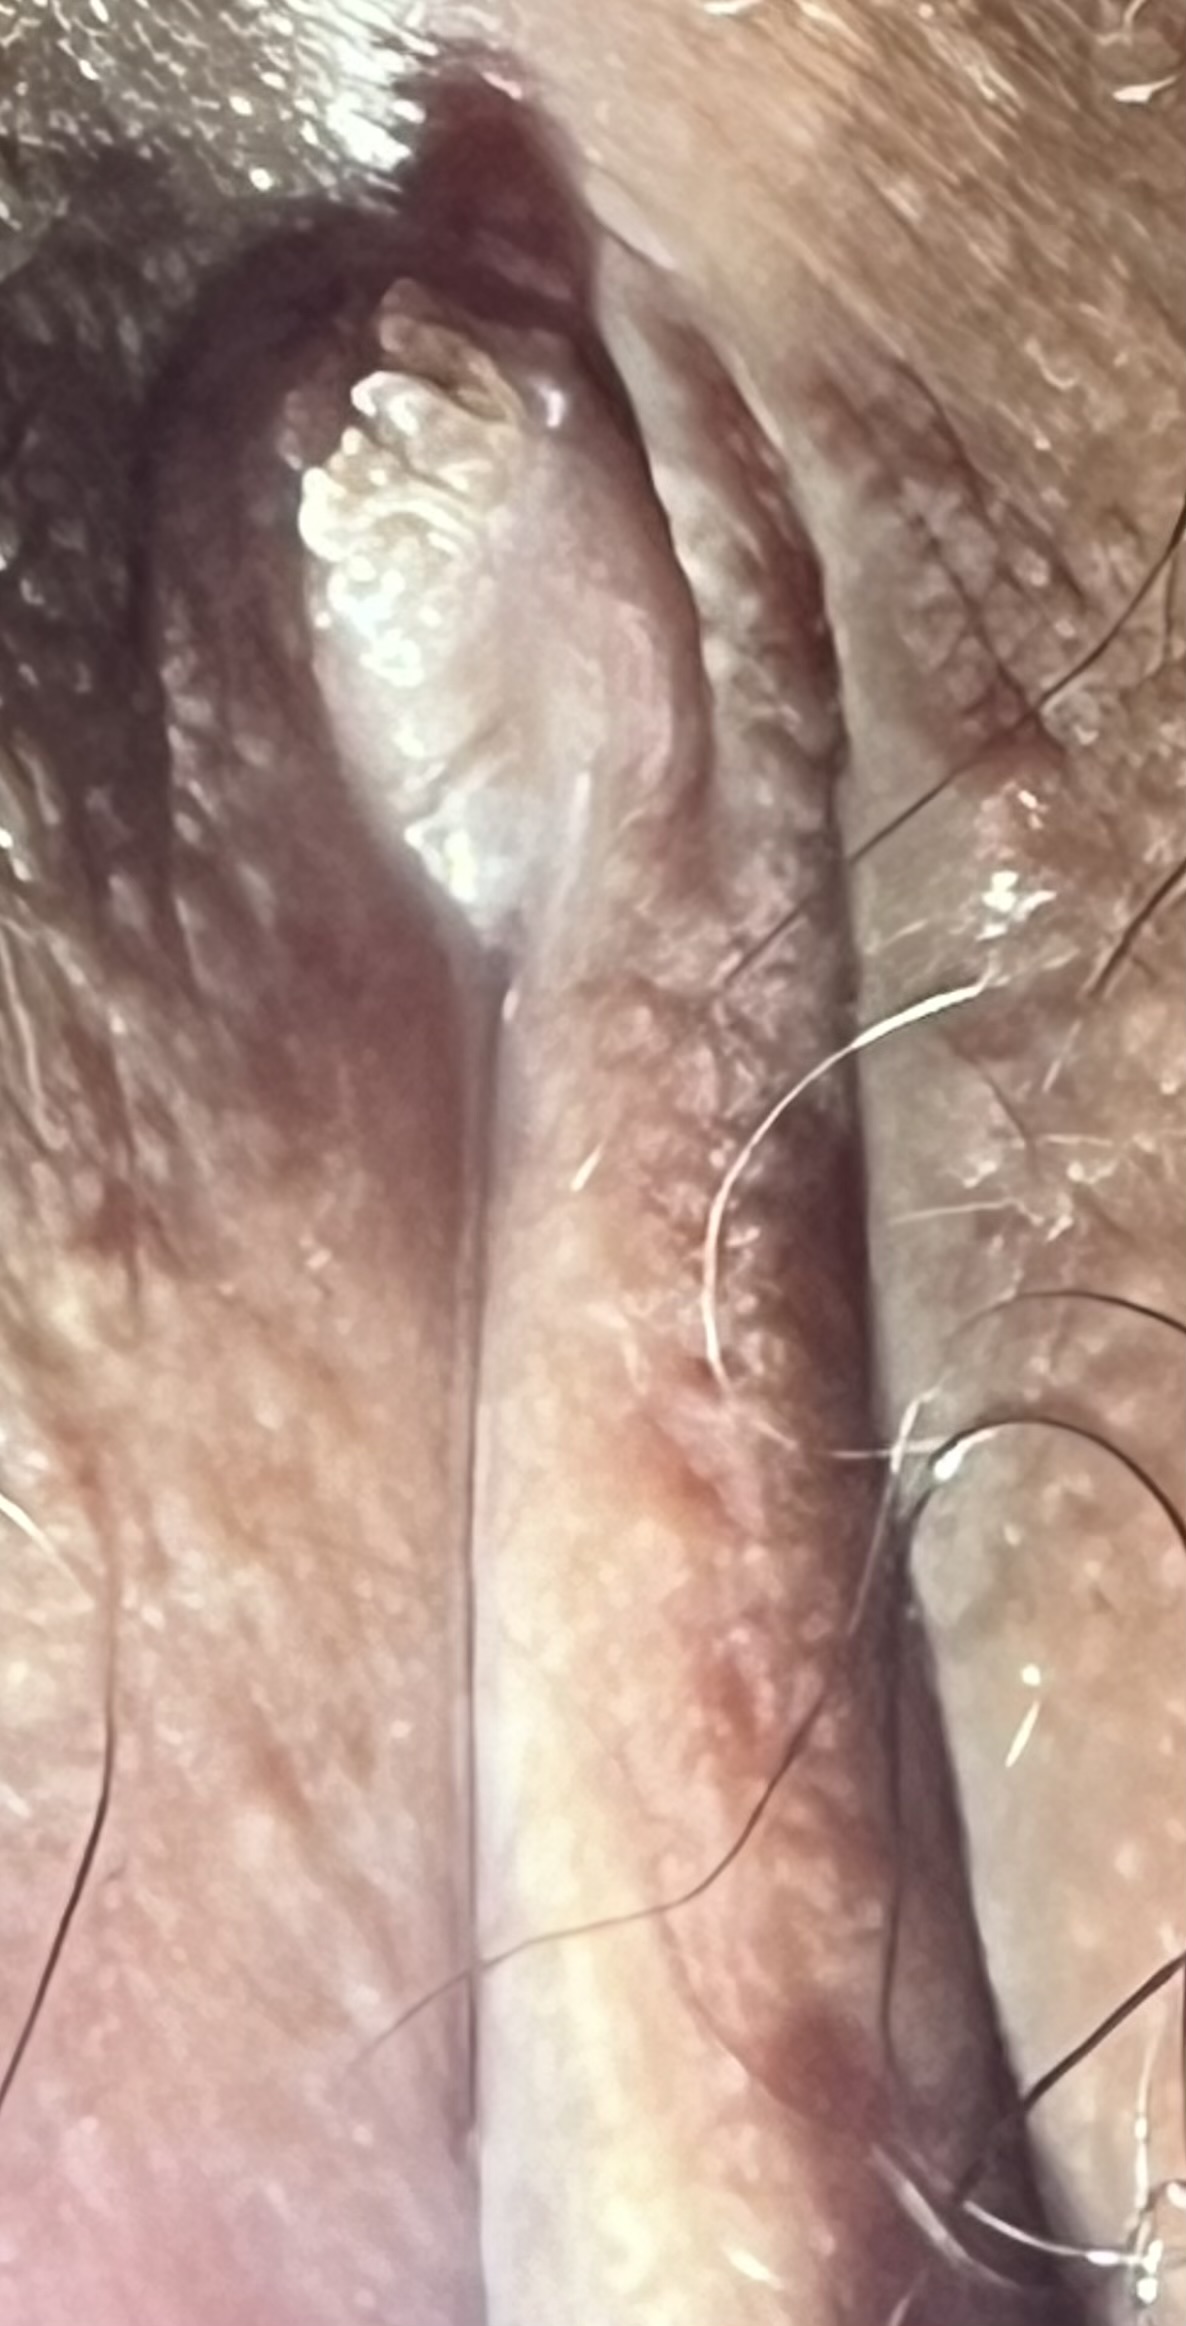

รบกวนสอบถามคุณหมอค่ะตอนนี้เครียดมาก2วันที่ผ่านมารู้สึกว่ามีติ่งๆอะไรเกิดขึ้นตรงอวัยวะเพศอยากทราบว่าลักษณะแบบในรูปนี้จะเรียกว่าเป็นหูดหงอนไก่รึป่าวค่ะ แล้วมันอัตรายมากไหมคะ มีอะไรกับแฟนนเก่าล่าสุดเมื่อ2เดือนที่แล้วค่ะ

ดูจากรูปที่ส่งมา เห็นเป็นติ่งเนื้อที่บริเวณอวัยวะเพศ ลักษณะคล้ายหูดหงอนไก่ หูดหงอนไก่เป็นโรคติดต่อทางเพศสัมพันธุ์ที่พบได้บ่อยขึ้น เกิดจากเชื้อไวรัส Human Papilloma Virus (HPV) การรักษาคือใช้ยา podophyllin หรือ trichloracetic acid จึ้อาทิตย์ละ 1-2 ครั้ง ประมาณ 4-6 อาทิตย์ จี้หรือใช้ไฟฟ้า หรือเลเซอร์ ซึ่งจะฉีดยาชาเพื่อไม่ให้เจ็บเวลาจี้ แนะนำหาหมอ และควรตรวจเลือดซิฟิลิสและเอชไอวี สามารถใช้สิทธิประกันสังคมหรือบัตรทองได้ครับ